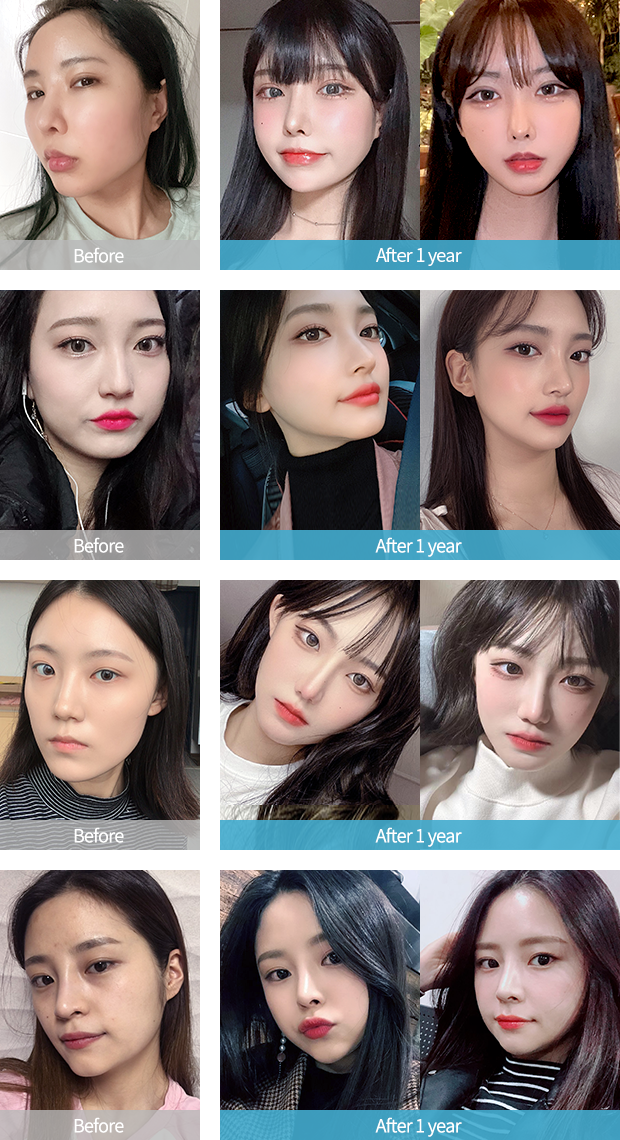

CCTV 운영

대리수술 NO

상담부터 진단, 수술까지 1인 원장시스템으로

CCTV가 운영되는 수술실에서

확실한 집도의실명제를 실천하고 있습니다.

집도의 확인

수술 실명제

CCTV 운영